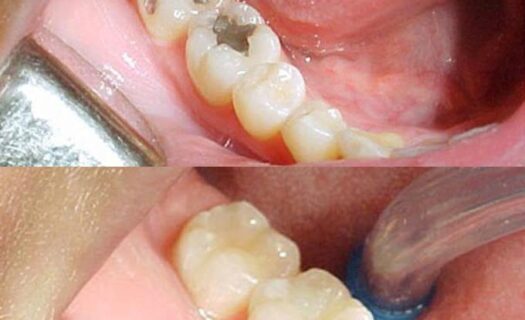

As restaurações dentárias estéticas são uma opção para corrigir imperfeições nos dentes, com objetivo de melhorar a aparência e a função dental. Elas podem ser feitas com diferentes materiais, como resina composta, porcelana e zircônia. A resina composta é o material mais comum para restaurações estéticas. É um material versátil que pode ser moldado diretamente na boca do paciente, oferecendo resultados de boa qualidade em casos de cáries pequenas, fraturas dentárias ou desgaste do esmalte. A resina composta também é mais barata em comparação com outros materiais de restauração.

Uma restauração estética é um procedimento odontológico que visa melhorar a aparência dos dentes, corrigindo imperfeições estéticas, como manchas, descolorações, dentes lascados, fraturados ou com formato irregular. Essas restaurações podem ser feitas com materiais como resina composta ou porcelana.

As facetas de porcelana são lâminas finas feitas de porcelana que são colocadas na parte frontal dos dentes para melhorar sua aparência. Já as restaurações de resina composta são feitas de um material compósito de resina que é moldado e esculpido diretamente nos dentes. Ambos os materiais têm suas próprias características e benefícios.